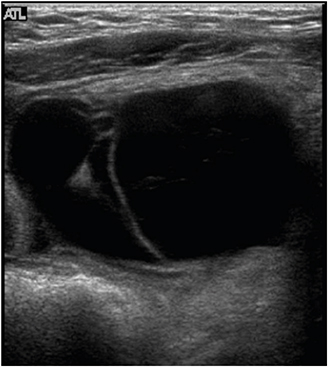

All patients underwent abdominal ultrasonography and computed tomography (CT) scans. In patient No. 7, these modalities showed a cystic mass, 9 cm in size, with multiple septa in the lower abdomen (Figs. 1, 2). An abdominal CT scan of patient No. 9 showed a huge multiloculated cystic mass with a septum; this mass occupied nearly the entire abdominal cavity and caused the displacement of the bowel to the left posterior abdomen.

Fig. 2

Abdominal computed tomography scan with intravenous contrast enhancement of patient No. 7, showing a multiloculated cystic mass with a thin wall occupying the lower abdomen.

Abdominal lymphatic malformations are very difficult to diagnose before surgery, with most patients diagnosed by postoperative biopsy. No specific radiologic findings can confirm abdominal lymphatic malformations before surgery. Abdominal ultrasonography or CT is necessary for accurate diagnosis before surgery, with these modalities providing information on lesion location and size and association with adjacent lesions. On abdominal ultrasonography, these lesions appear as hypoechoic cystic masses with a round wall separated by echogenic septa in the cystic space [37]. Abdominal CT scans provide more information before surgery about lesion location, size, and association with adjacent lesions. Typically, shading of the contents is homogeneous, with CT scans showing a single or polycystic mass with thin walls, as well as showing the relationship of the lesion with adjacent organs and blood vessels [319]. Abdominal magnetic resonance imaging (MRI) does not provide more information than ultrasonography or CT about lesion location, but it may be helpful in diagnosing complications such as hemorrhage. CT scanning is useful diagnostically, but ultrasonography and MRI may be better for children because of low radiation exposure. The differential diagnosis of abdominal lymphatic malformations includes other cystic abdominal masses, such as choledochal cysts, urachal cysts, ovarian cysts, renal cysts, intestinal duplications, abdominal lymphoma, simple mesenteric cysts, and pancreatic pseudocysts [82021].